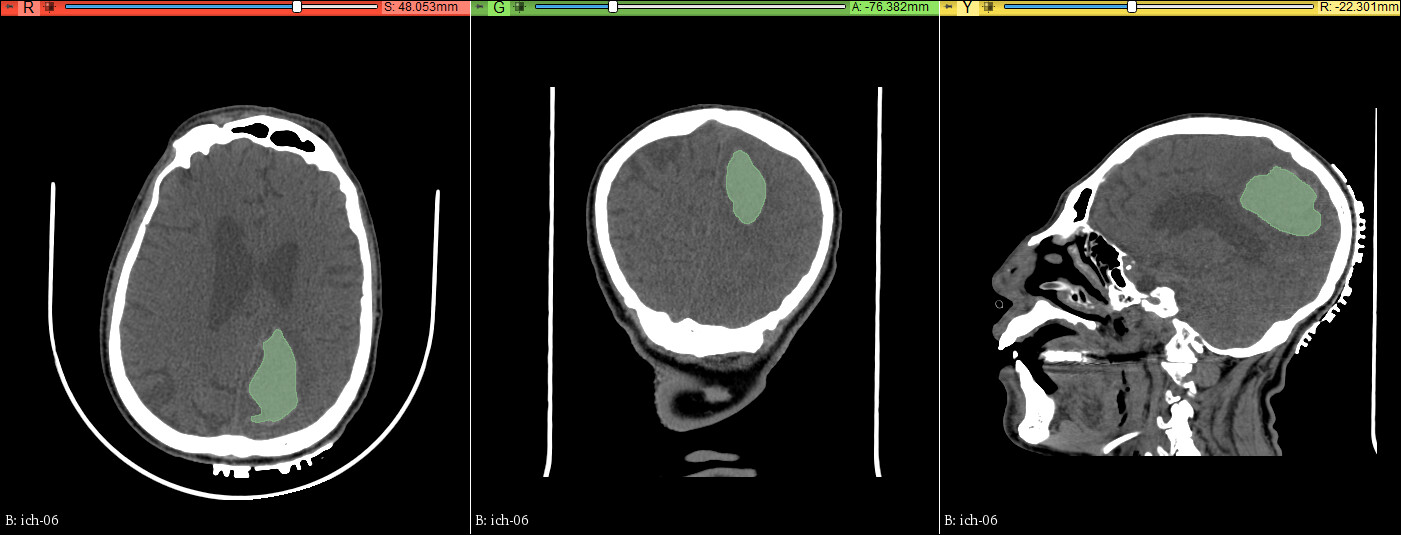

练习数据:示例数据MRBrainTumor2

数据:005分割练习数据→脑出血→分水岭-顶叶脑出血定位帖